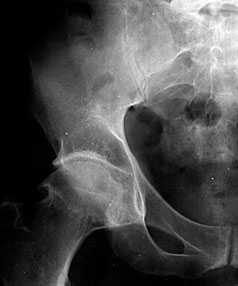

Рис. 1. Обзорная Rо-графия тазобедренного сустава в прямой проекции.

Деформирующий остеоартроз II ст. по Kollgren. Крупные остеофиты на краях суставных поверхностей. Грибовидная деформация бедренной головки

В поздних стадиях заболевания (соответствует 3-4 стадии ОА по Kellgren) отмечаются:

• прогрессирующее сужение суставной щели

• формирование различной формы и размеров остеофитов на краях суставных поверхностей вертлужной впадины, бедренной головки, отчего она со временем приобретает грибовидную форму. В средней части вертлужной впадины возможно формирование клиновидного остеофита, который может обусловить латеральное смещение бедренной головки

• углубление вертлужной впадины может быть связано с развитием остеофитов; протрузия ее возможна на фоне остеопороза или истончения костей, составляющих дно вертлужной впадины

• выраженный субхондральный остеосклероз. Проявляется в первую очередь в области крыши вертлужной впадины, затем в верхнем отделе бедренной головки

• в далеко зашедших случаях - уменьшение в объеме и уплощение суставной поверхности бедренной головки на фоне выраженной кистовидной перестройки костной ткани, чередующейся с участками субхондрального остеосклероза. Костные кисты могут быть единичными или множественными. Возникают они в верхней части вертлужной впадины или в зоне наибольшей нагрузки на суставную поверхность бедренной головки

• асептический некроз бедренной головки

• подвывихи бедренной кости чаще вверх и латерально, реже вверх и медиально

• уплотнение костной ткани и укорочение шейки бедренной кости.